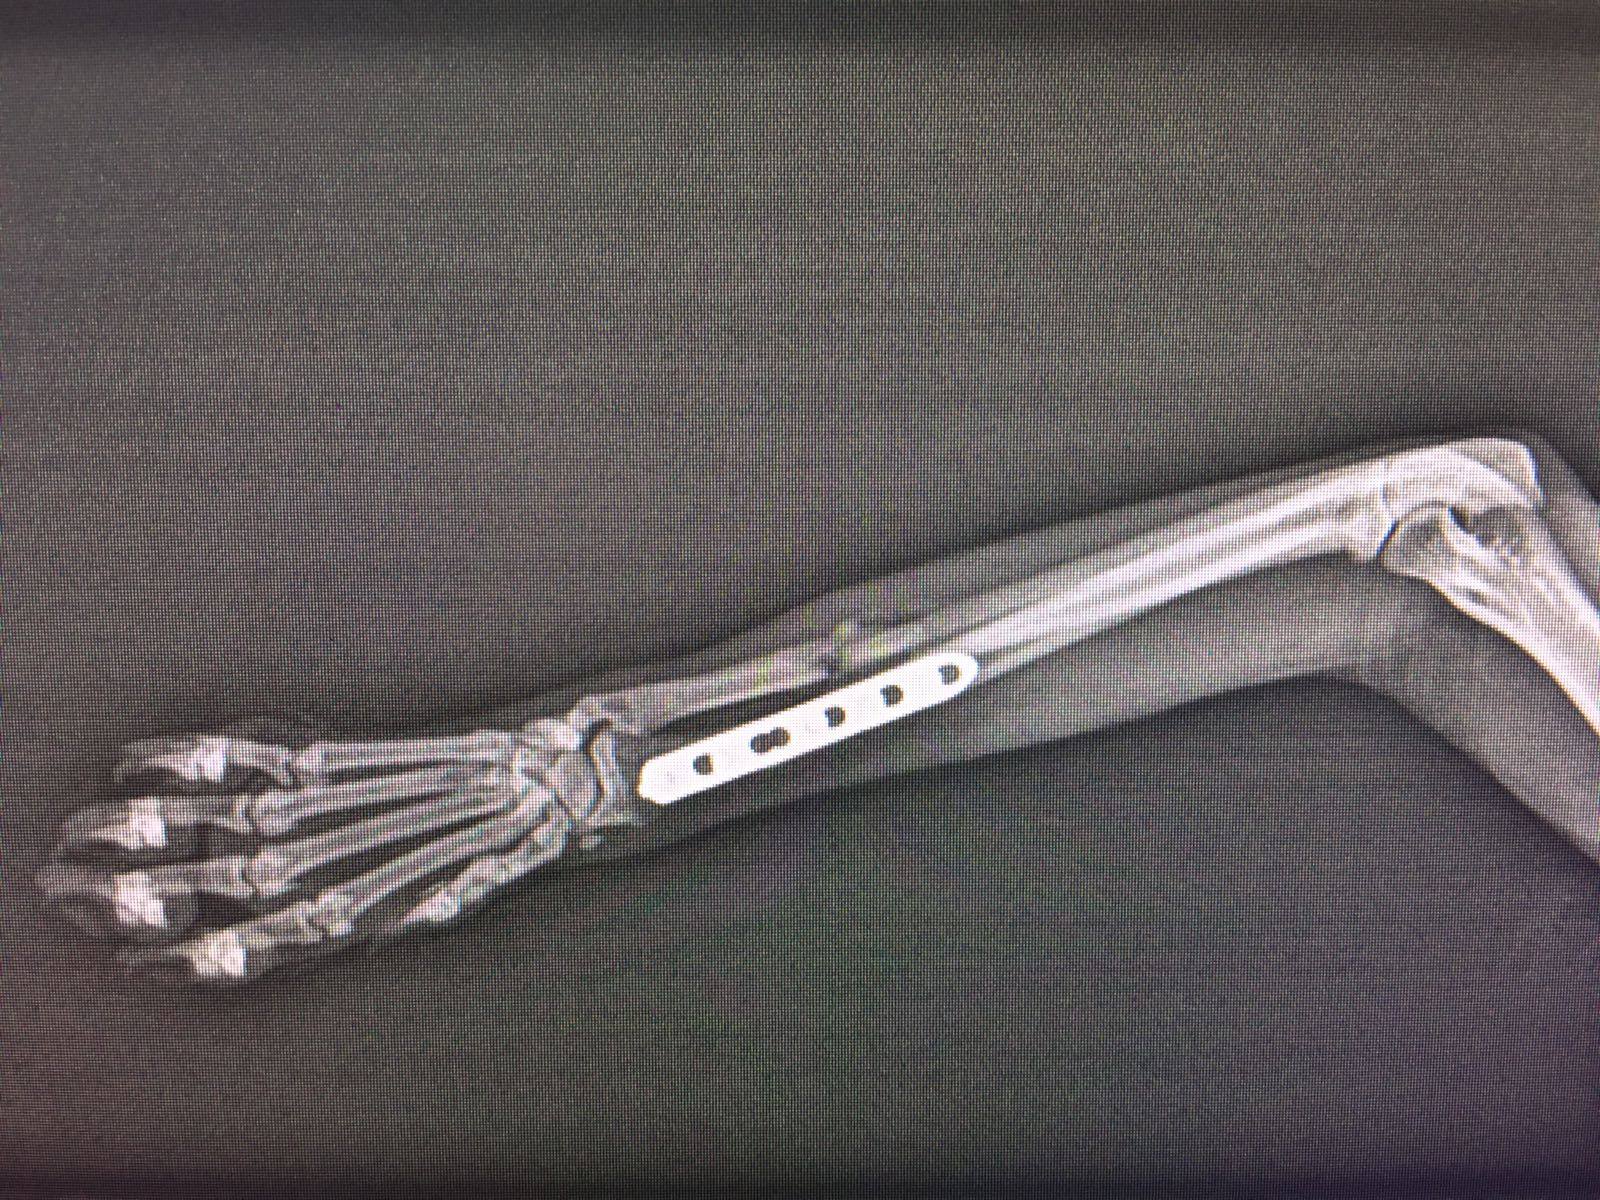

Ayer operaron a Pipo, la cirugía aunque complicada porque era antigua y los huesos se habían girado por el paso del tiempo y manipulaciones hasta que llegó al hospital, fue bien. Aquí tenéis unas fotos de la placa que se le ha puesto.